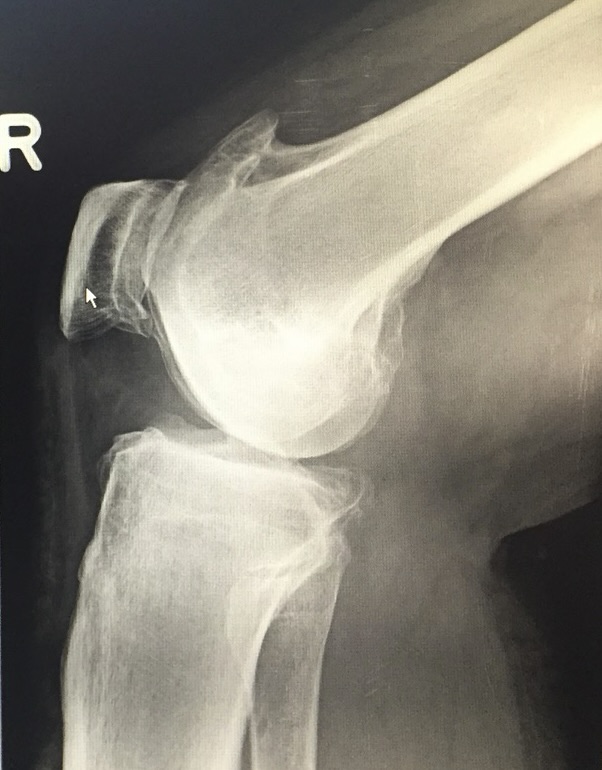

- Προχωρημένη οστεοαρθρίτιδα γόνατος

- Αποτυχία συντηρητικής αγωγής

- Ιδιαίτερη ανατομία ή προηγούμενες επεμβάσεις